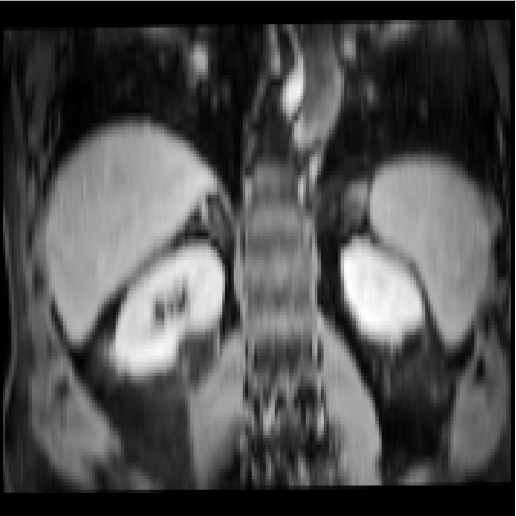

Abdomen MR-CT

The data was compiled from public studies of the cancer imaging archive (TCIA) [23] that contained paired scans of both MR and CT from the same patients. In particular, 16 MR and CT scans from the following studies, TCGA-KIRC [24], TCGA-KIRP [25], and TCGA-LIHC [26], are included in Learn2Reg - that cover routine diagnostic scans and follow-up imaging for kidney surgery. The data has been resampled to an isotropic resolution of 2mm, and cropped and padded to achieve voxel dimensions of 192x160x192. We have also manually traced 3D segmentation masks for the liver, spleen, left and right kidney. All scans were pre-aligned using a groupwise affine registration based on the deeds-linear algorithm [27]. Additional unpaired and segmented training data from two further challenges - BCV-CT [12] and CHAOS-MR [28, 29] - were provided for pre-training.